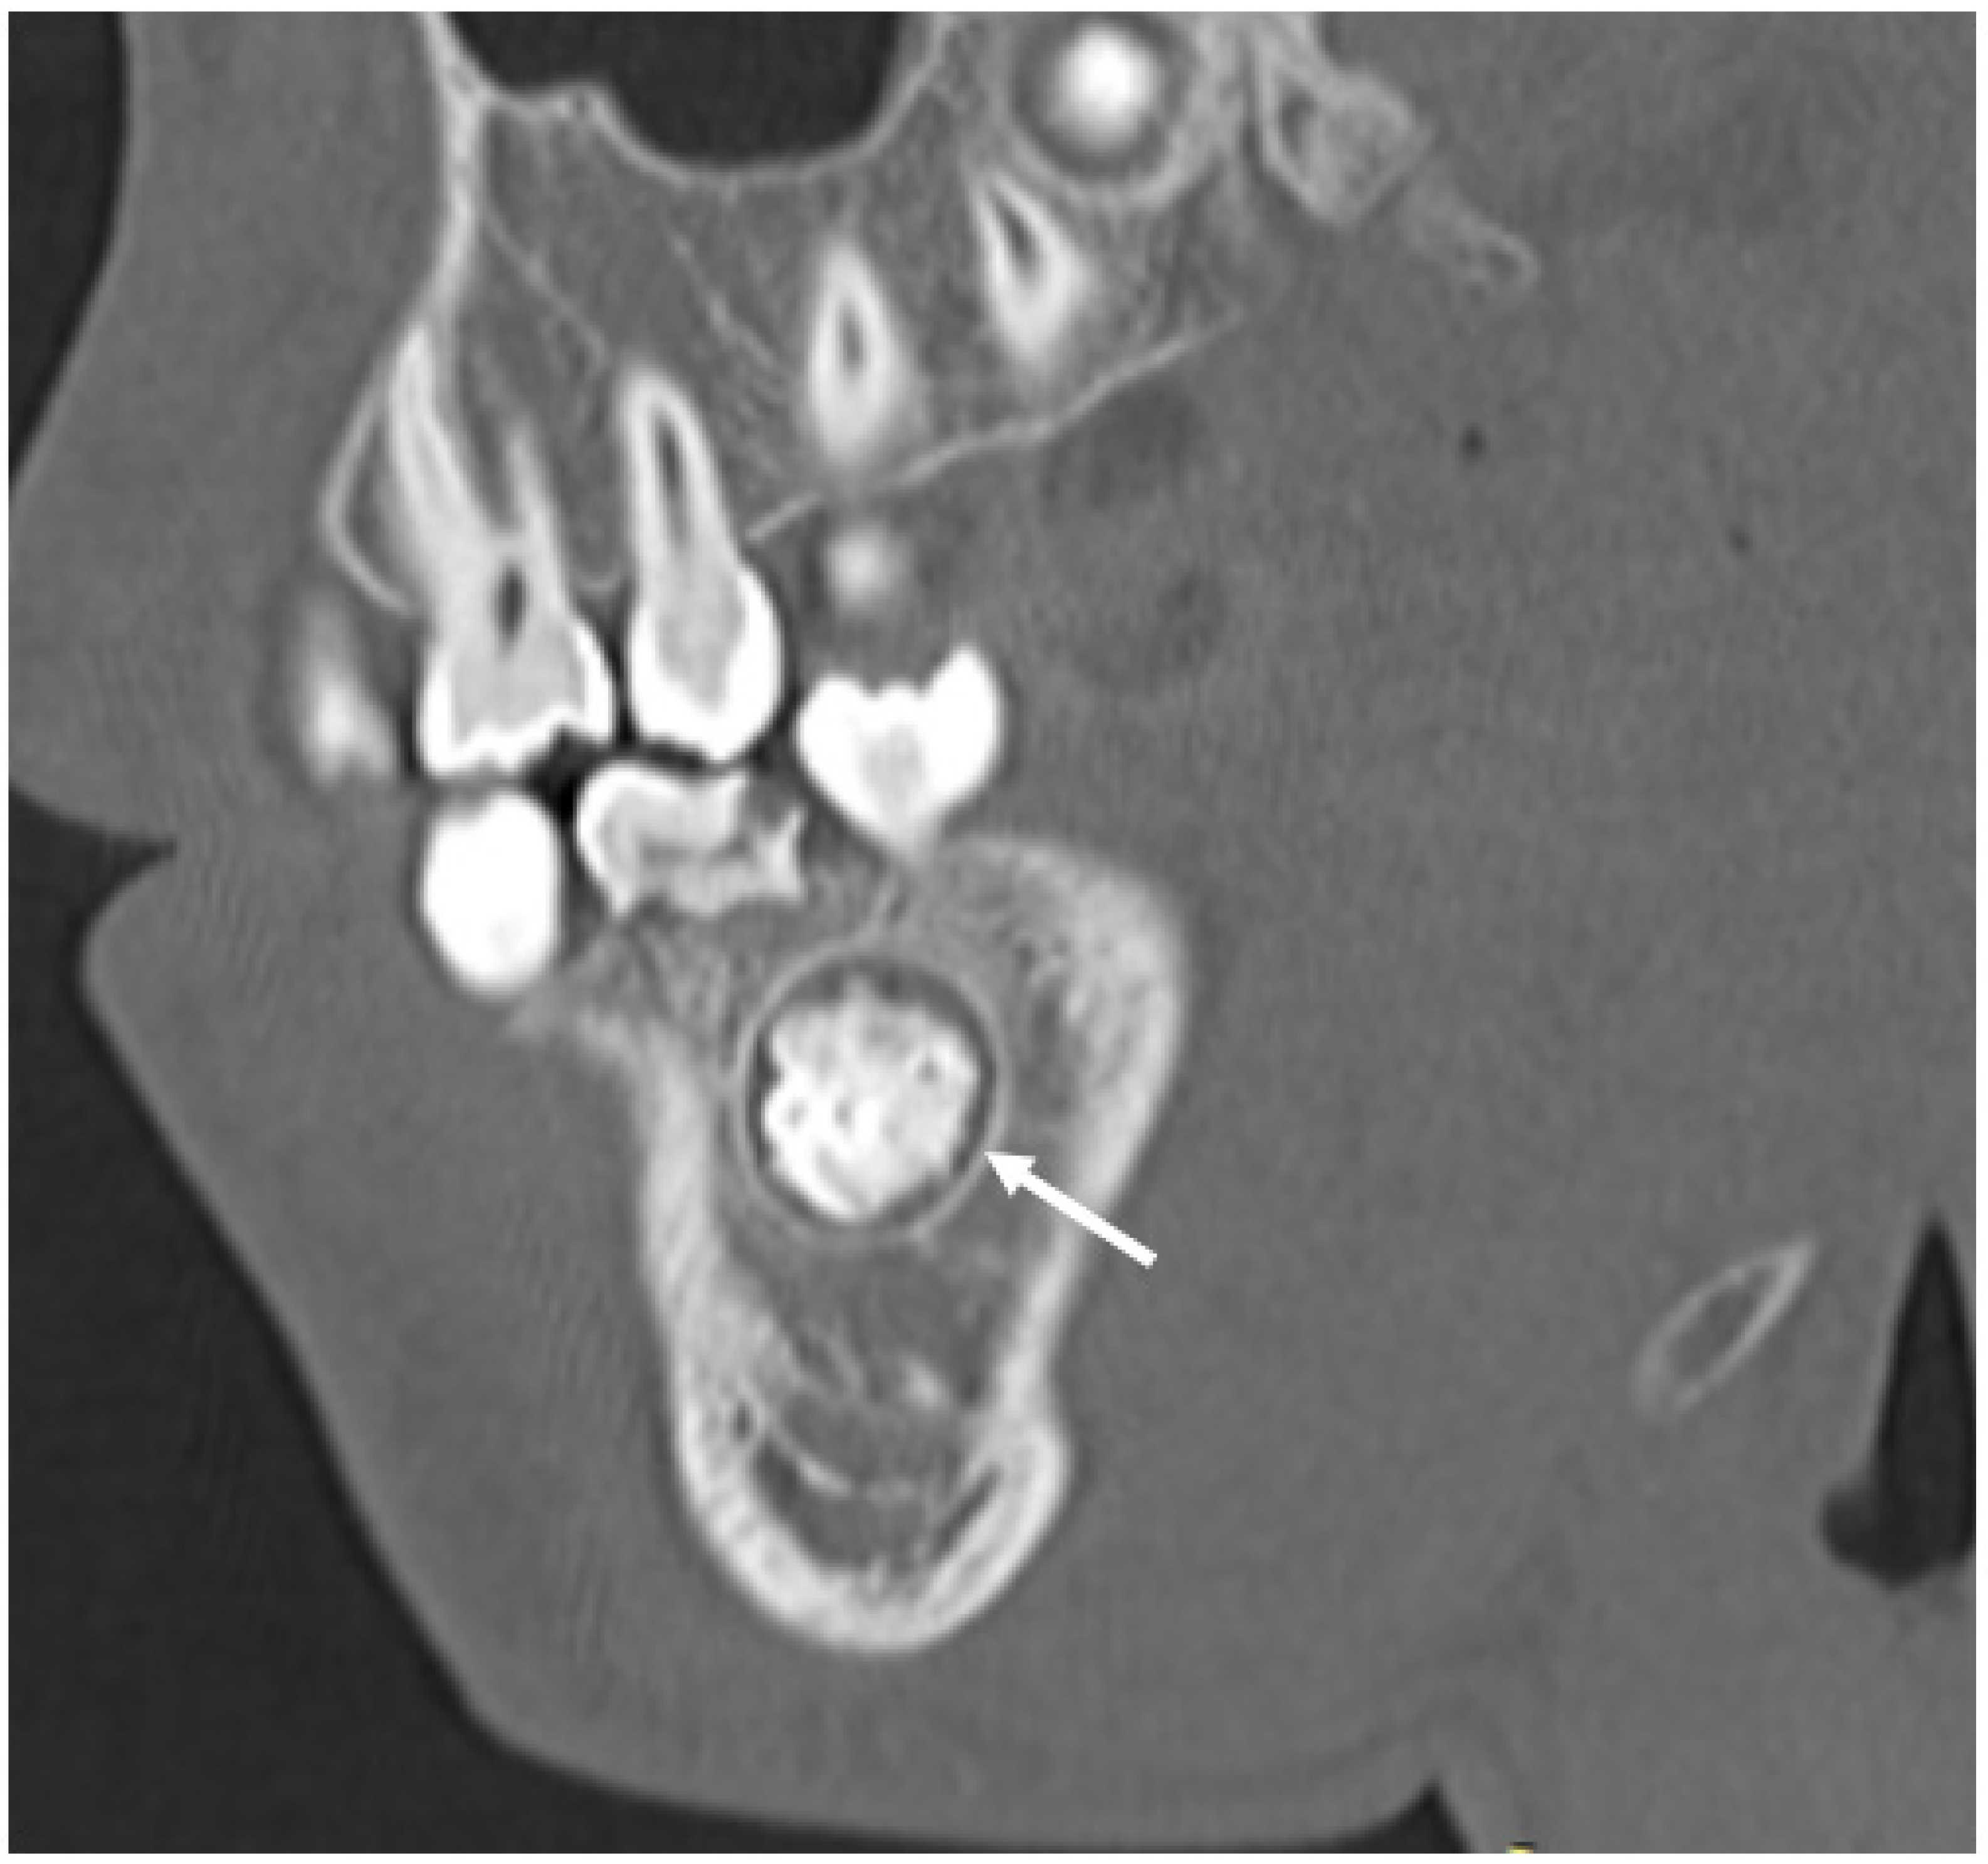

3.5.2. Dental Decay Radiologic Correlations